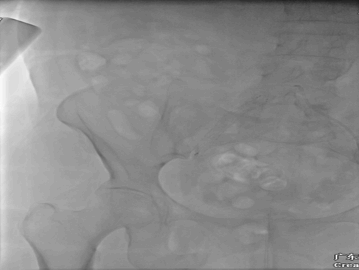

术中DSA:

双侧造影证实真腔DSA